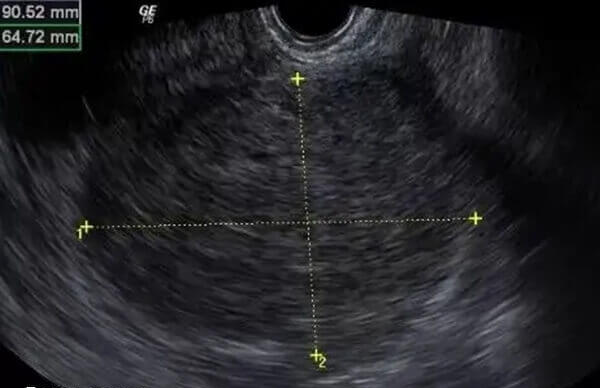

DHA可增加子宫内膜血流灌注,促进白血病抑制因子等与胚胎着床相关的因子表达,提高胚胎着床率。临床观察显示,补充DHA后子宫内膜厚度可能增加1-2mm,为胚胎着床创造更有利的条件。